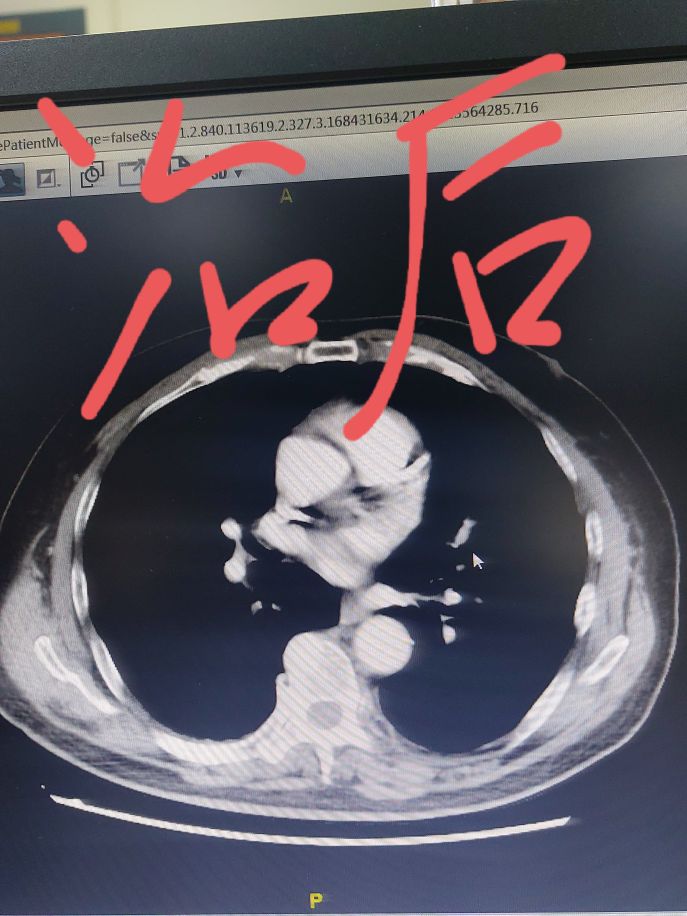

我给大家看一个具体的病例,这位患者几个月之前在我这里住院,当时左上肺有一个肿瘤,同时肺门纵隔淋巴结比较大,要说手术也不是不行,关键这位患者心脏还不好。这样的分期直接手术效果不太确定,所以我给他设计了先做两个周期药物治疗,然后再手术的策略。大家可以看一下下面的截图,通过穿刺这个患者病理是一个倾向于肺鳞癌,我给用的化疗加免疫药物的方案,进行了两个周期治疗,从我发的照片可以看到,做了两个周期治疗之后,肿瘤明显就减小了。

在治疗肿瘤的同时,心脏也在逐渐的调整恢复,这次达到了手术的要求,上周把手术给做了。手术后切下来的左上肺叶,我把肿瘤的位置剖开。肿瘤的位置流出来的都是那种棕黄色的像脓一样的东西,这是坏死的东西,当时我就给家属看,我说这个肿瘤细胞根据我的经验来看可能全被杀死了,咱们等等病理看看是不是这样。